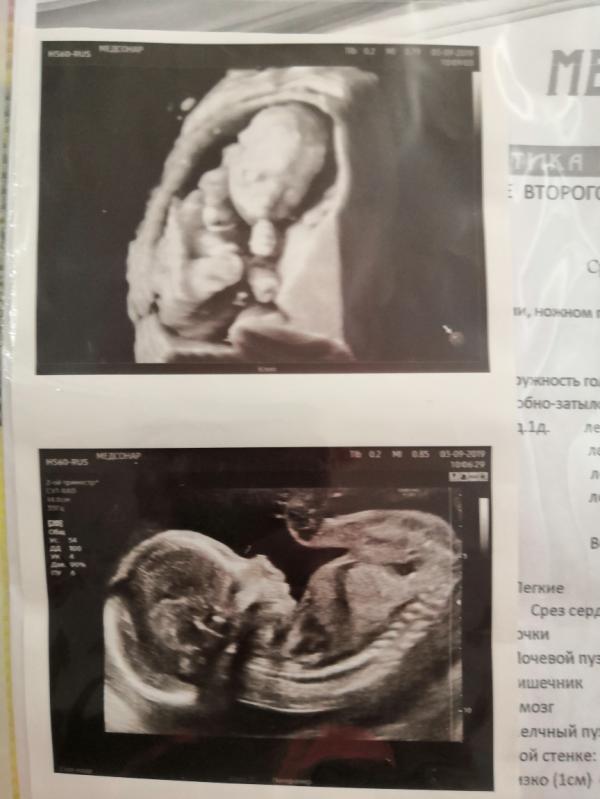

@lera.morgacheva все его хвалят, а нам он почти на 500гр с весом ошибся и срок неправильно посчитал 🤷🏼♀️ но мы не 3д делали УЗИ, может аппарат другой сейчас, но тогда слабый был, муж ими раньше торгавал и разбирается, единственное как человек понравился на общение. Но у вас фото что надо👌😊.

😍😍😍😍😍 У меня куча фото, но одной стороны или другой😅 никак не могли сфоткать прям так как у вас😊такая память💕